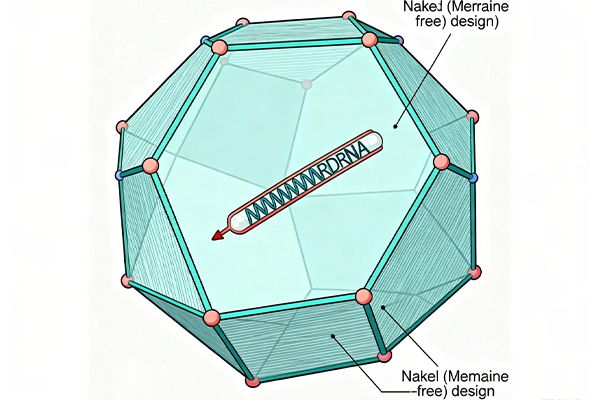

- Naked Icosahedral Capsid: Unlike some viruses, norovirus lacks a lipid membrane (making it “naked”). Its outer shell is an icosahedron—a 20-sided spherical structure made of protein— which protects its genetic material.

- Single-Stranded RNA (ssRNA): The virus’s genome is ssRNA that functions directly as messenger RNA (mRNA). When it invades a host cell (specifically cells in the small intestine), host ribosomes use this mRNA to build a long “polyprotein,” which viral enzymes then split into smaller proteins needed for replication.